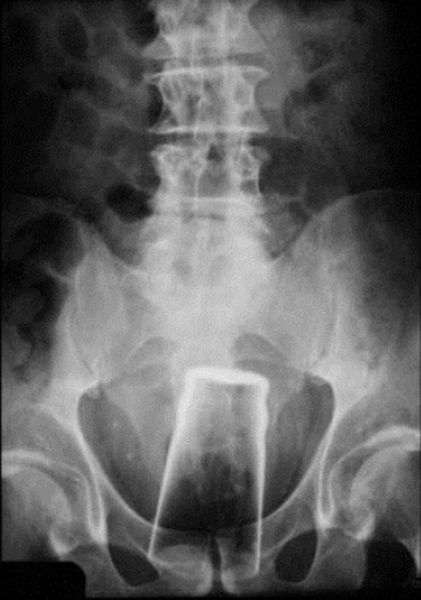

Pint Glass